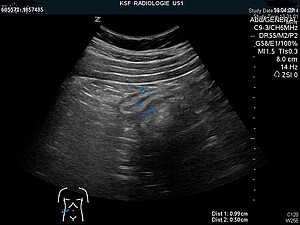

Meist ist die Diagnose der Appendizitis eine klinische Diagnose, welche durch den Untersuchungsbefund (Abtasten des Bauchraums) gestellt wird. Zur weiteren Sicherung der Diagnose werden Entzündungswerte im Blut (Erhöhung der weissen Blutkörperchen und das sogenannte C-reaktive Protein CRP) untersucht. Die Diagnose kann durch eine Ultraschalluntersuchung oder eine Computertomographie unterstützt werden.

Insgesamt sind 16 Mitarbeitende beteiligt! Auf der Notfallstation wird von einer Pflegefachperson Blut abgenommen und eine Assistenzärztin oder ein Assistenzarzt macht die erste Untersuchung. Die Radiologiefachperson lhilft der Radiologin oder dem Radiologen bei der Ultraschalluntersuchung des Bauches. Die Chirurgin oder der Chirurg entscheidet anhand der Untersuchung, der Blutwerte und der Ultraschalluntersuchung, ob es sich um eine Appendizitis handelt und ob eine Operation erfolgen muss. Damit eine Operation durchgeführt werden kann, benötigen die Petienten eine Vollnarkose, die entsprechenden Medikamente werden von den Narkoseärzten (Anästhesisten) und von der Pflegefachperson Anästhesie verabreicht. Eine OP-Pflegefachperson bereitet die Operation vor und kontrolliert die Lagerung im OP-Saal. Die Chirurgin oder der Chirurg und eine Assistenzärztin/ein Assistenzarzt operieren, während eine OP-Assistenz ihnen die Instrumente reicht. Auch die OP-Assistenz braucht eine Zudienung, da sie mit den Chirurgen steril am Operationstisch arbeitet und manchmal zusätzliche Instrumente benötigt. Nach der Operation werden in der Sterilisation die Instrumente gereinigt und wieder sterilisiert. Der Operationssaal muss gereinigt werden, der entfernte Wurmfortsatz wird von den Pathologen untersucht. Wenn die Patientin oder der Patient wach ist, wird sie von den Pflegefachperson der Station abgeholt und in sein Zimmer gebracht.